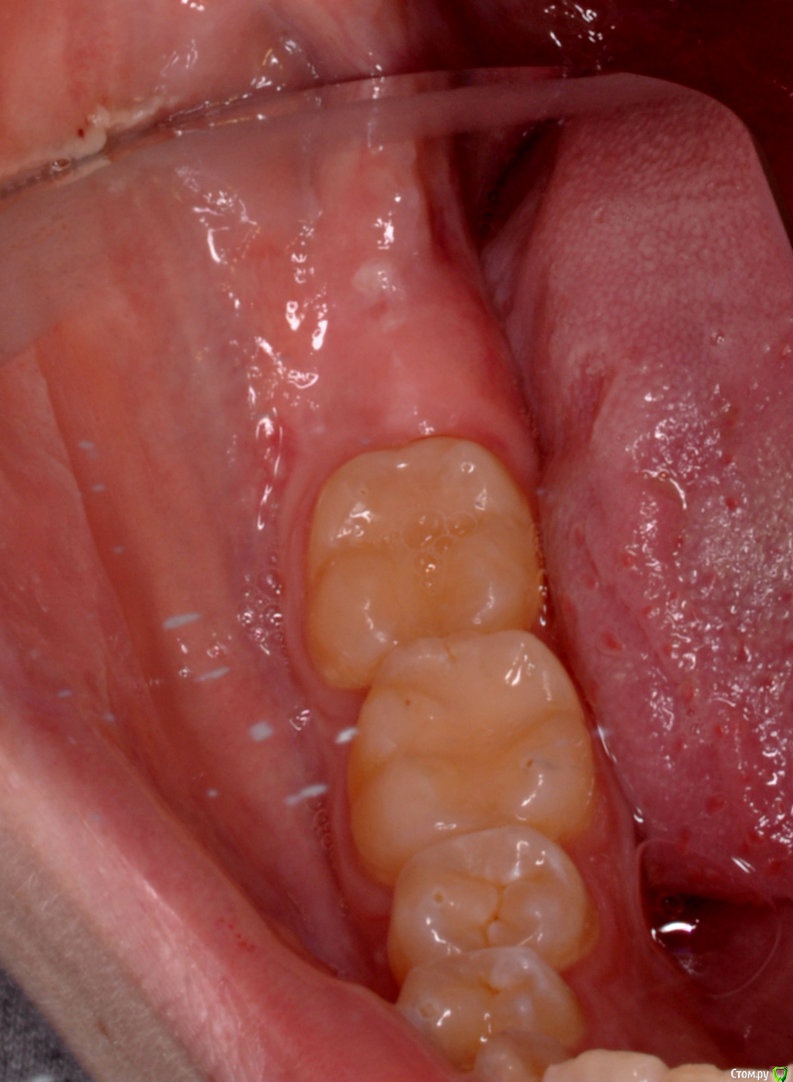

колесников Опубликовано 2 апреля, 2017 Автор Поделиться Опубликовано 2 апреля, 2017 Тройной лоскут , вид через 5 -7дней. Снимок "до". И благодарность за скорое заживление 6 Ссылка на комментарий

колесников Опубликовано 16 апреля, 2017 Автор Поделиться Опубликовано 16 апреля, 2017 Иногда кажется ,что лоскут выделить язычно не возможно и наглухо ушить не удасться,особенно в случаях когда 8ка полностью прорезалась. Это только так кажется. Ссылка на комментарий

колесников Опубликовано 17 апреля, 2017 Автор Поделиться Опубликовано 17 апреля, 2017 (изменено) В данном случае развёрнутый. Опрокинутый когда 8ка не прорезалась,самый простой вариант. Да,в щели вижу всю проблему вторичного инфицирования,для прикрытия вероятного расхождения краев раны за 7кой,делаю второй лоскут. Изменено 17 апреля, 2017 пользователем колесников Ссылка на комментарий

колесников Опубликовано 6 мая, 2017 Автор Поделиться Опубликовано 6 мая, 2017 Воспользовался случаем попрактиковаться в выделении язычного лоскута. Разрез поверхностный,далее расщепление и выделение.По поводу лоскута без графта. Дважды пришлось так поступить. В первом случае расхождение краев за 7кой с образованием щели и застревание пищи. Во втором случае мезиально все герметично,дистально (?) щель,при зондировании -пусто. Итого: лоскут без графта-так себе вариант. Ссылка на комментарий